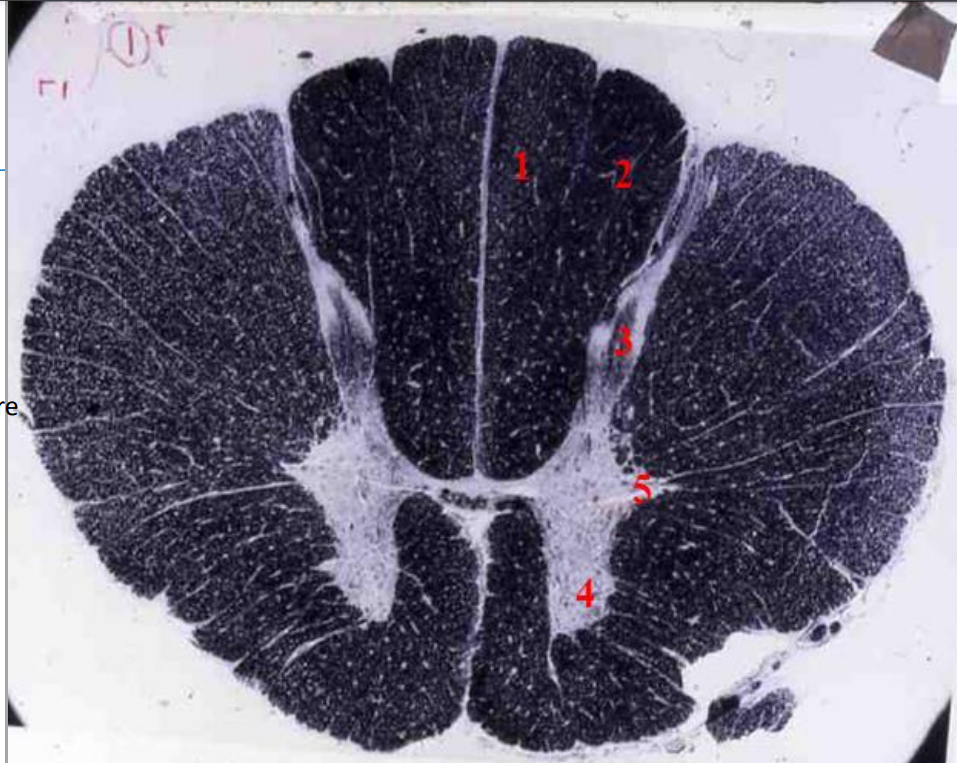

11

Q

indentify the weigert

A

cervical cord

- fibre tracts are larger

- grey matter is large

- brachial plexus

- no lateral horn

12

fasiculus gracilis

13

fasciculus cuneatus

14

posterior horn

15

anterior horn